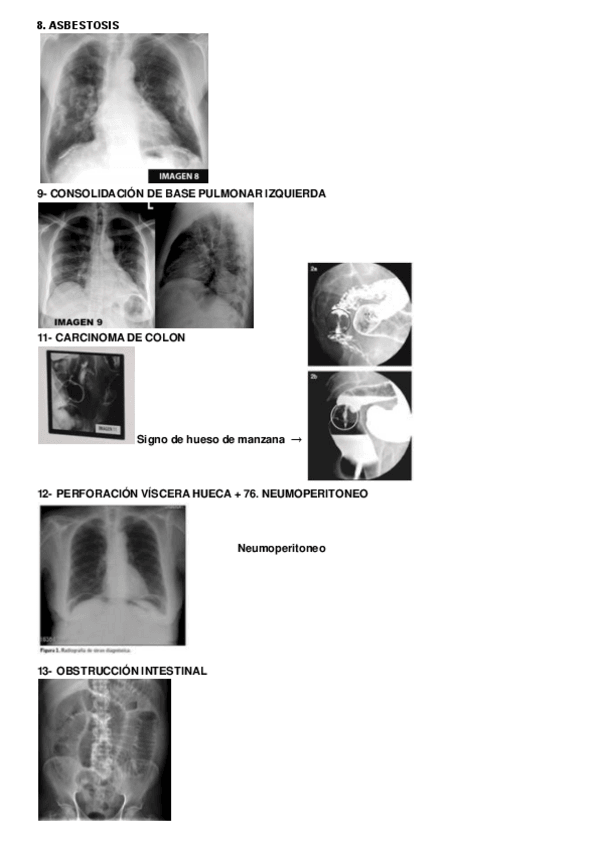

Casos-ABDOMEN.pdf

He publicado nuevos apuntes de 3º Diagnóstico por imagen: IMAGENES-RAYOS.pdf

He publicado nuevos examenes de 3º Diagnóstico por imagen: IMAGENES-RAYOS-ACTUALIZADO.pdf

He publicado nuevos examenes de 3º Diagnóstico por imagen: IMAGENES-EXAMENES-DXI.pdf